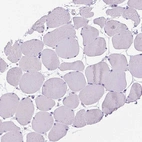

Immunohistochemical staining of human placenta shows moderate to strong cytoplasmic positivity in extravillous trophoblast.